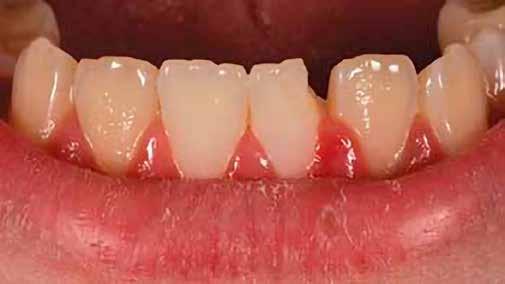

A posterior fogak direkt kompozit restaurációja az egyik leggyakrabban végzett beavatkozás a fogászatban. Az elmúlt években kiemelt figyelem irányult az elérhető eredmények optimalizálására, különös tekintettel a II. osztályú kavitás dobozának (Class II box) kialakítására, és a polimerizációs zsugorodásból eredő feszültség kezelésére. A téma körüli széles körű szakmai diskurzus ellenére van egy olyan lépés, amely gyakran nem kapja meg a kellő figyelmet: a mechanikai formázás protokollja. A mechanikai formázás alatt a restauráció kontúrjának kialakítását, a felesleges kompozit eltávolítását értjük a marginális szélekről, illetve ide tartozik a végső polírozás is. Ez a folyamat három fő lépésre bontható: a felszín oxigén által gátolt, nem polimerizált rétegének eltávolítása, a durva finírozás és a végső polírozás. Jelen publikációban részletesen bemutatjuk ezeket a lépéseket, valamint egy klinikailag hatékony megközelítést vázolunk fel a direkt posterior kompozit restaurációk befejezésére.

2. ábra: A páciens egy nem megfelelő I. osztályú ezüstamalgám töméssel és II. osztályú szuvasodással jelentkezett. A fog izolálása kofferdám alkalmazásával történt.

3. ábra: A preparálás, a bondozás és a kompozit felvitele után. (Megjegyzés: némi kompozit túlfolyás látható a mesiális doboz axiális falain).

4. ábra: A durva finírozás után a restauráció pereme sima és anatómiailag is megfelelő.